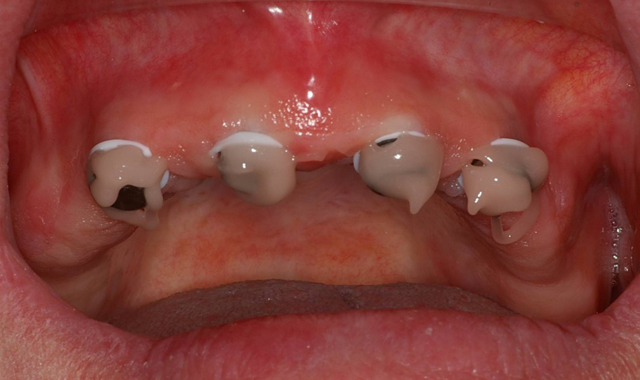

The patient’s existing maxillary denture was relieved in the areas of the attachments (Fig. 7) to avoid putting direct pressure on the implants. The implants were allowed to heal for about four months, at which point impressions would be taken to start fabrication of the definitive prosthesis. Utilizing Panasil® monophase Medium (Kettenbach USA) body impression material in a thermoplastic tray (Fig. 8), a full-arch impression was taken of the maxillary arch picking up the LOCATOR Impression Copings (ZEST Dental Solutions).

Fig. 7 Fig. 8

Once the impressions, relations, shade and opposing model were forwarded to the dental lab, the metal-reinforced, palate-free overdenture was initiated.

Approximately three to four months later, the previously made metal-reinforced overdenture with relieved areas for the housings was tried in to confirm comfort and fit. Any interference that was detected between the denture base, attachments and housings was checked and eliminated (Fig. 9).

Fig. 9 Fig. 10